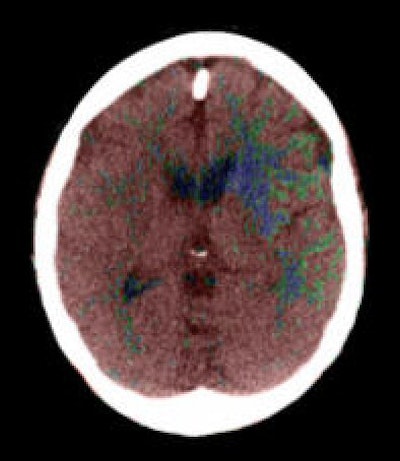

| Top to bottom: Perfusion CT images overlaid on CT source images of a 73-year-old male patient. The patient was scanned 30 minutes after the sudden onset of right hemiparesis with an NIHSS of 20. Above, cerebral blood flow (CBF) map shows a blue-color area of low CBF (range: 0-12 mL/100g/min) in the basal ganglia on the left side, which corresponds to the irreversibly infarcted tissue. Note the peripheral area displayed as green, which corresponds to the penumbra region (range: 12-24 mL/100 g/min). In the image below, cerebral blood volume (CBV) map does not demonstrate a clear delineation of the infarcted region in comparison with the CBF map. In the bottom image, mean transit time (MTT) map shows a slightly larger abnormality than seen on the CBF map. Images courtesy of Dr. Sotirios Bisdas. |